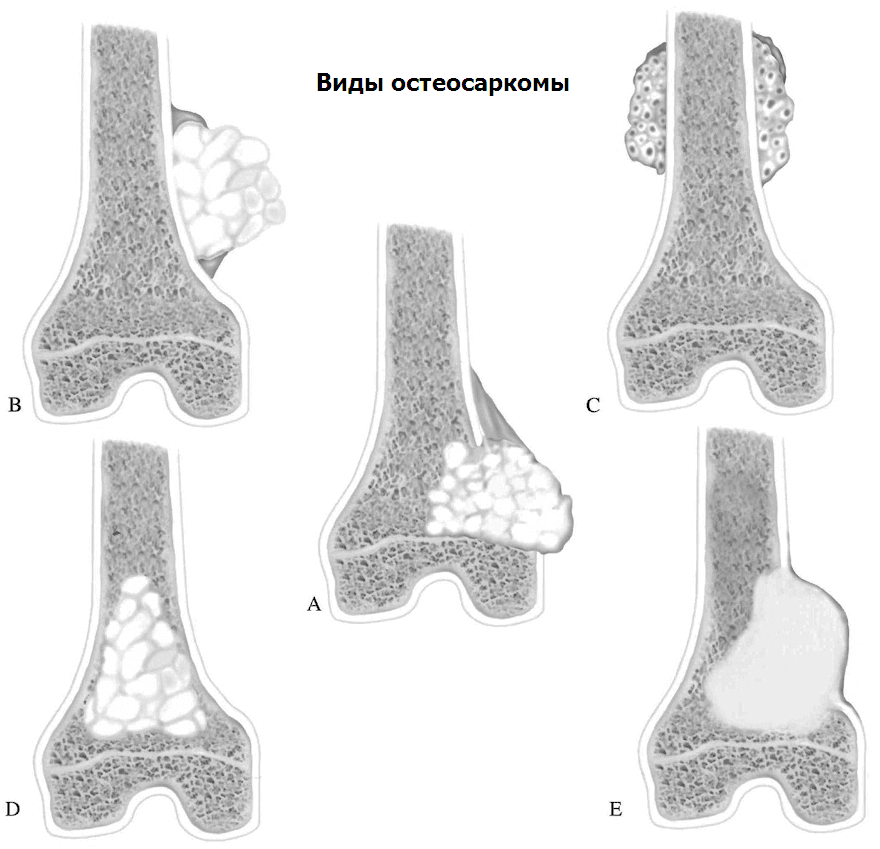

Рентгенологическая картина остеогенной саркомы кости - 98 фото